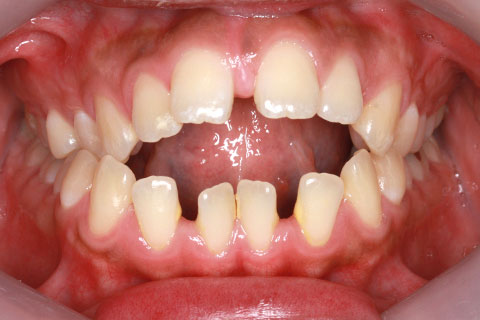

症例1

治療前

開咬症の症状

奥歯は咬んでいるが前歯は咬んでいない状態。奥歯でしか咬み合わず、奥歯への負担が非常に大きくなります。また、幼少期の舌の癖や指しゃぶりが主な原因で、そのまま大人になると治療が難しくなる可能性があります。

年齢・性別

23歳女性

治療期間

1年4ヶ月

抜歯

なし

治療費

80万(税込)

備考

マルチブラケットを用いた矯正治療

治療内容

前歯の開口を顎間ゴムにて改善

施術の副作用(リスク)

舌の癖や鼻疾患がある時は、後戻りを起こすことがあります。